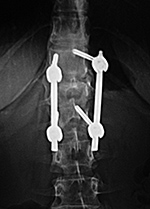

| Extensive lumbar spine fusion with pedicle screws and rods |

| A laminectomy has been performed from T12-L5. Pedicle screws and rods are at L3-S1 from the initial lower lumbar spine fusion. Later surgery added pedicle screws and rods at T12-L3, and L3-L5 with a crosslink at L2. |